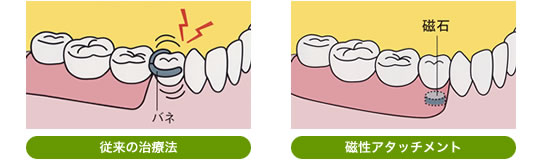

残っている"数本の歯"と装着する"入れ歯"に専用の磁石を取り付け入れ歯を安定させる方法です。磁石の大きさは米粒より小さく、安全性と耐久性があります。

磁石は強い吸着力を持っていますが、横からの無理な力がかかると外れるようになっているので、歯根にとてもやさしい構造です。

- バネを使用しないので審美的

残っている歯に引っ掛けるバネがないので、残っている歯にも負担がかからず、取り外しも簡単です。バネによる入れ歯は、バネのかかった歯に負担がかかり、グラグラさせたり、汚れがつきやすく虫歯の原因になります。また、バネがないので、見た目が自然で若々しい口元になります。歯が1本も残っていない方でも、インプラントと組み合わせることが出来ます。